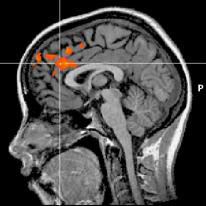

But Hedgcock’s study is the first to actually show it happening in the brain using fMRI images that scan people as they perform self-control tasks. The images show the anterior cingulate cortex (ACC) — the part of the brain that recognizes a situation in which self-control is needed and says, “Heads up, there are multiple responses to this situation and some might not be good” — fires with equal intensity throughout the task.

This image shows brain activity when people exert self-control. Credit: University of Iowa

However, the dorsolateral prefrontal cortex (DLPFC) — the part of the brain that manages self-control and says, “I really want to do the dumb thing, but I should overcome that impulse and do the smart thing” — fires with less intensity after prior exertion of self-control.

He said that loss of activity in the DLPFC might be the person’s self-control draining away. The stable activity in the ACC suggests people have no problem recognizing a temptation. Although they keep fighting, they have a harder and harder time not giving in.

The researchers gathered their images by placing subjects in an MRI scanner and then had them perform two self-control tasks—the first involved ignoring words that flashed on a computer screen, while the second involved choosing preferred options. The study found the subjects had a harder time exerting self-control on the second task, a phenomenon called “regulatory depletion.” Hedgcock says that the subjects’ DLPFCs were less active during the second self-control task, suggesting it was harder for the subjects to overcome their initial response.